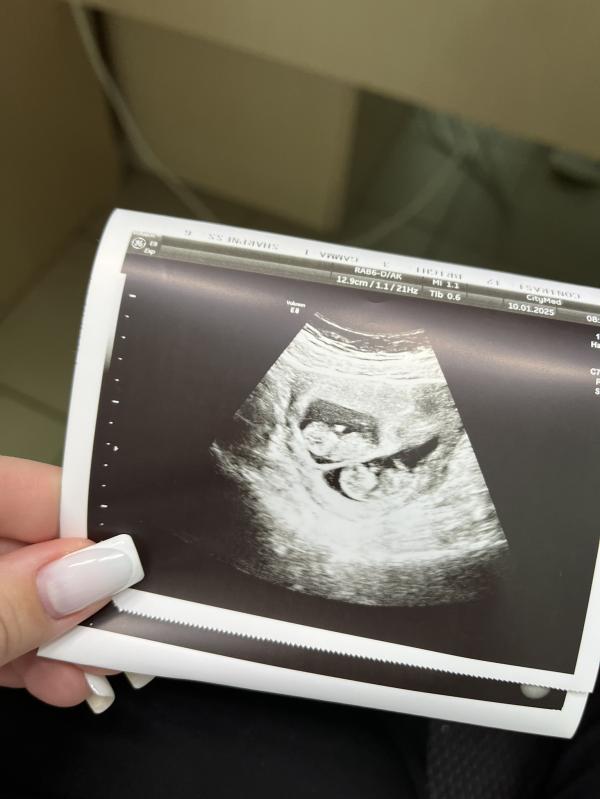

Последнее фото самое интересное, лежат как в плацкарте😄🥹😍

На последнем фото 11 недель😍